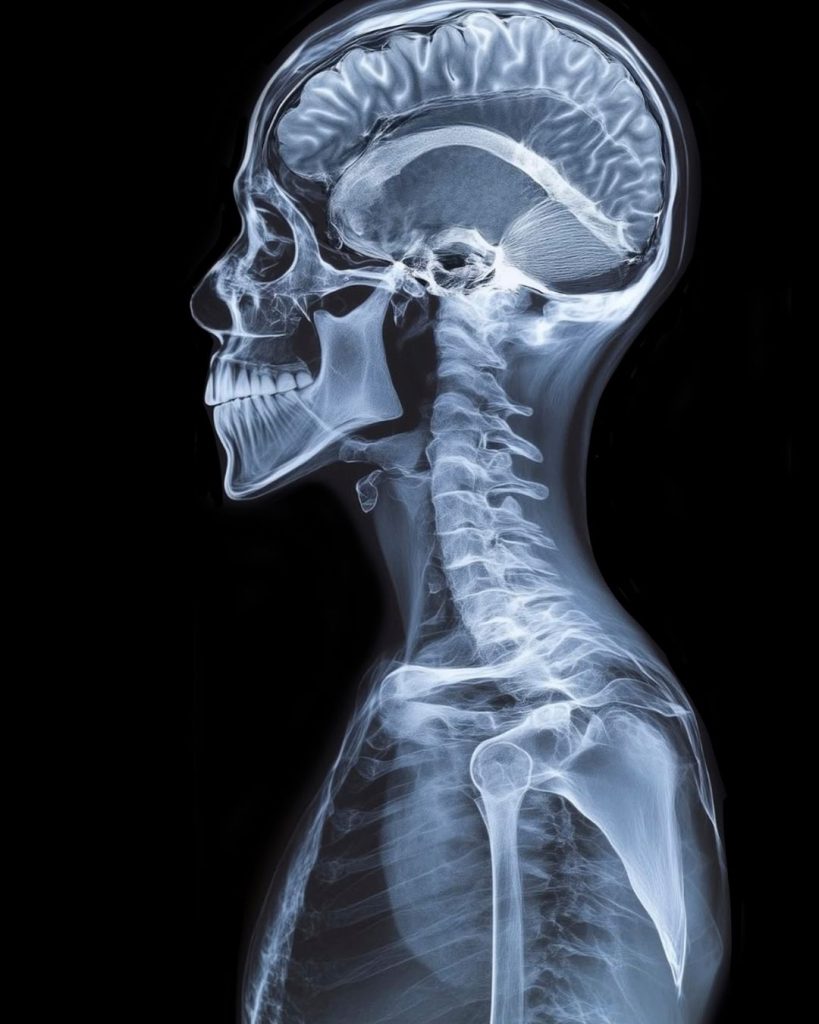

Addressing the Root Cause of Neck Pain

Most neck pain is related to problems in the cervical spine—whether from poor posture, repetitive strain, acute injury, or daily stress. Common signs that your neck pain may benefit from chiropractic care include:

Chiropractic care offers effective treatment for a wide range of neck conditions, addressing both acute injuries and chronic degenerative disorders. Here is a comprehensive list of cervical spine conditions that can benefit from chiropractic intervention: